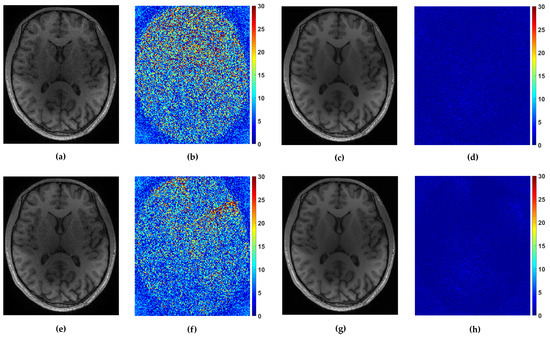

Figure 7. Reconstruction of axial-2 from randomly and uniformly sampled measurements from 4 coils. (a,c) Reconstructed images with P-LORAKS and FCLaTV method respectively from randomly sampled measurements with their (b,d) corresponding errors. (e,g) Reconstructed images with P-LORAKS and FCLaTV method respectively from uniformly sampled measurements with their (f,h) corresponding errors.

For the multi-coil reconstruction scenario, we used a T1 weighted brain image axial-2 from [38], shown in Figure 2, and measurements gathered from 4 coils with known given sensitivity profiles. We incorporate random and uniform sampling trajectories with sampling rate of 14% per each coil. For both trajectories, the proposed FCLaTV achieved lower RLNE values reported in Table 1. Figure 7 shows visual comparison of reconstructions between FCLaTV and P-LORAKS methods.